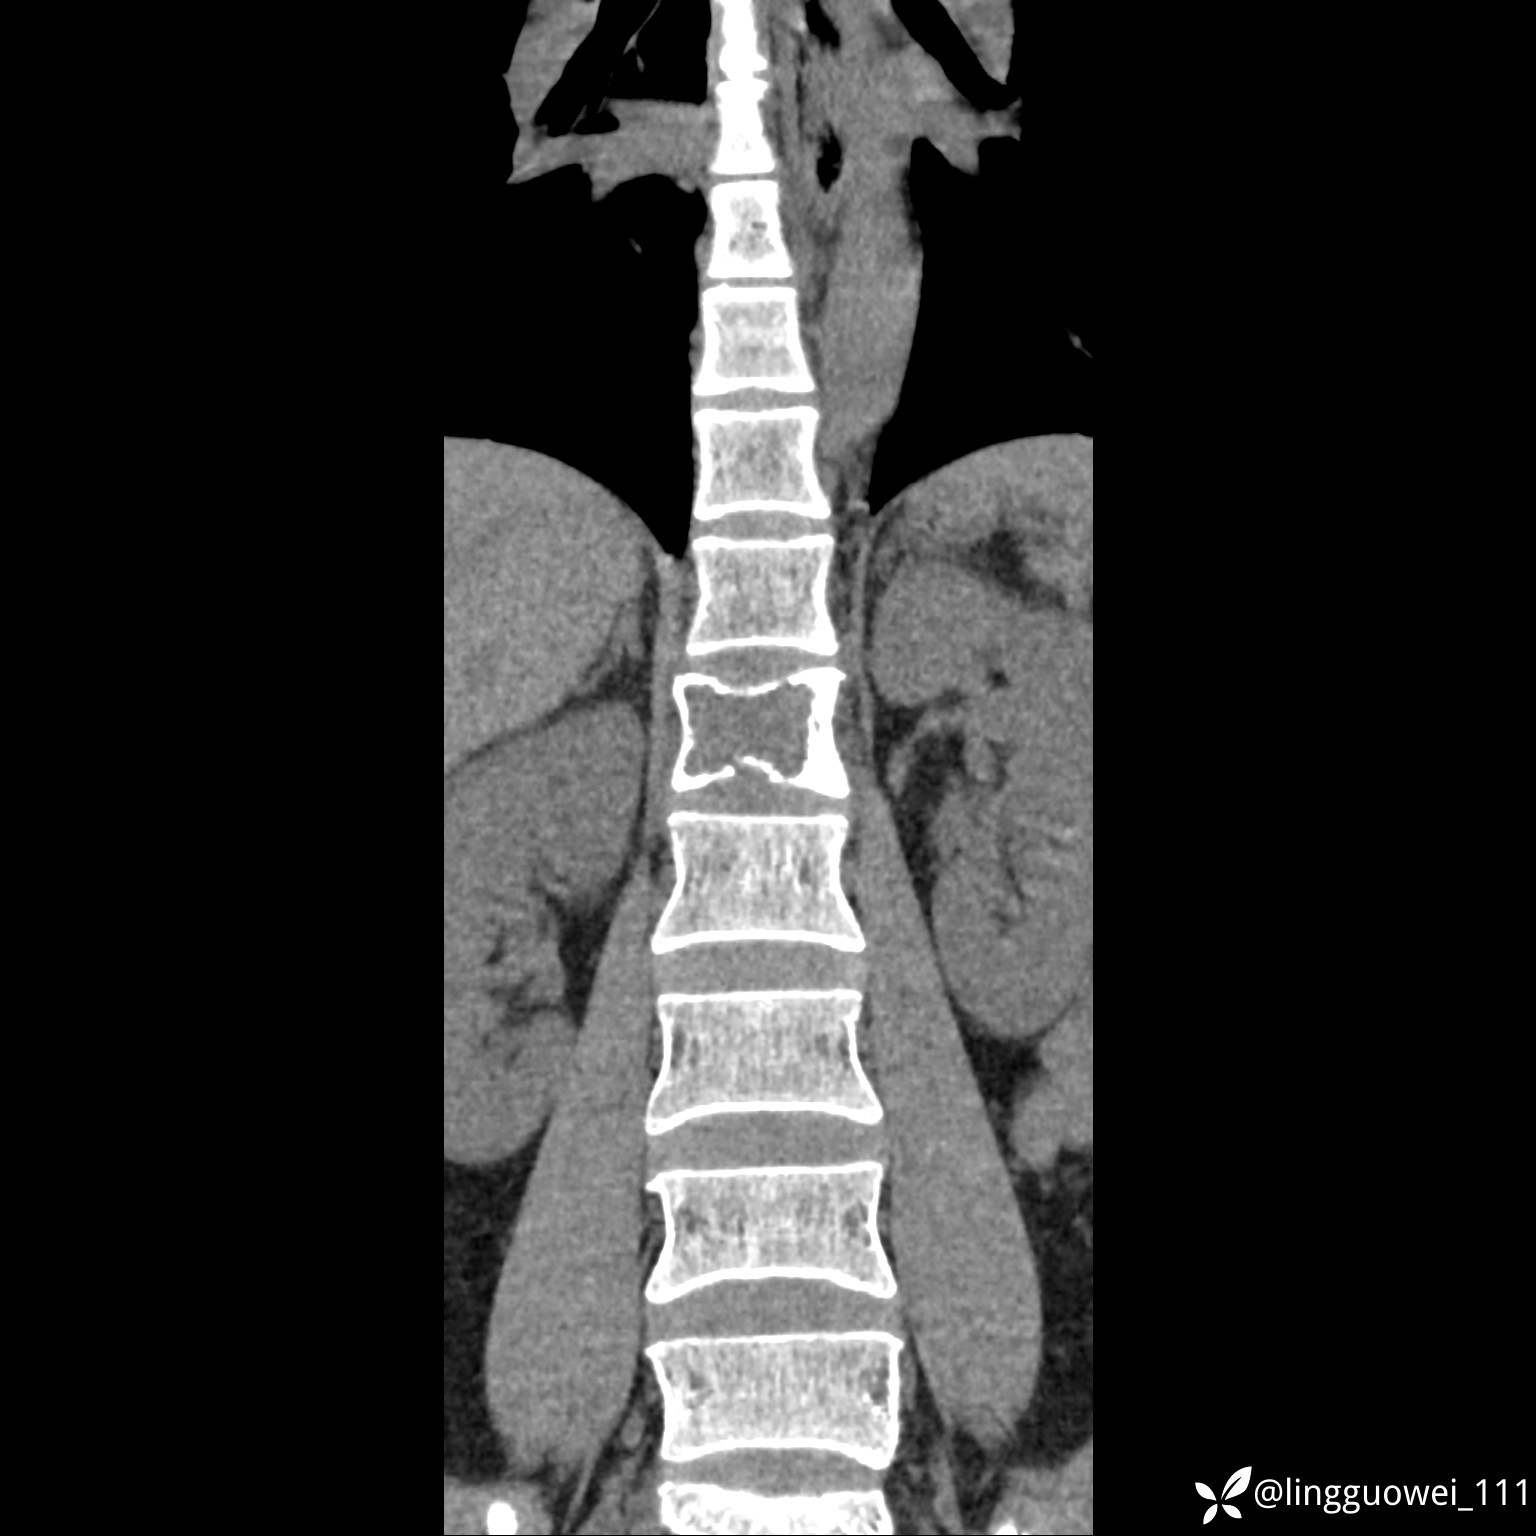

病例女,39岁,腰痛来诊,只有CT可能要鉴别诊断,而MR可以定性吗?

患者性别:女

患者年龄:39岁

主诉:腰痛